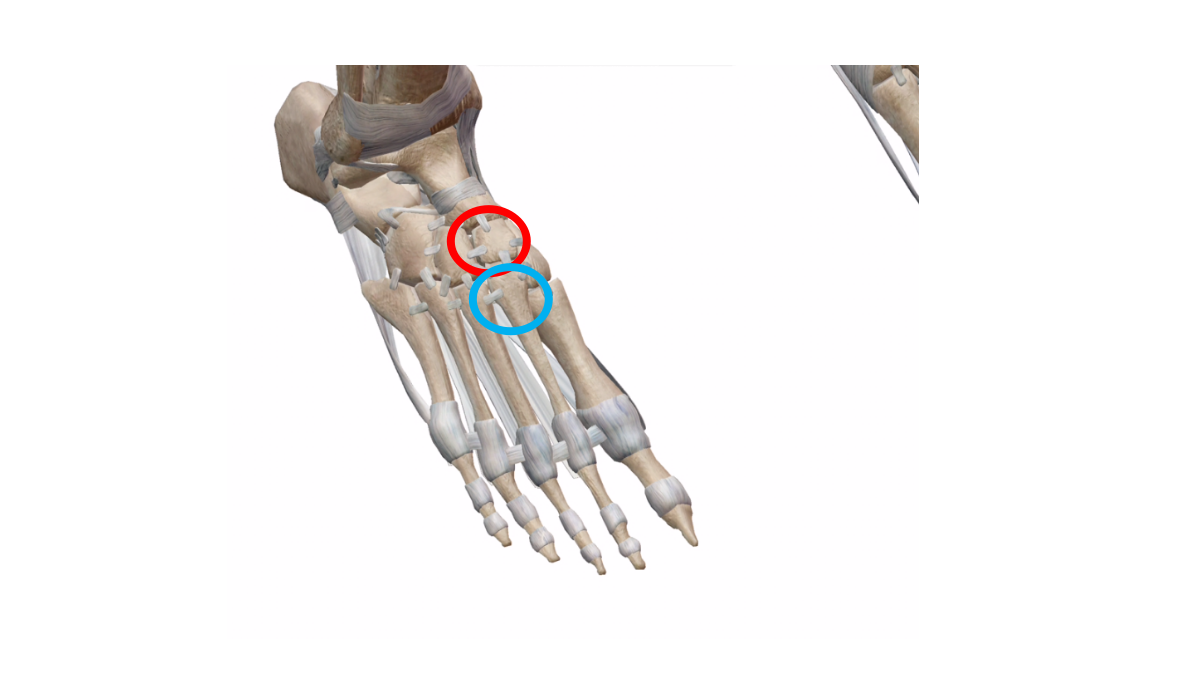

話しは出来ますが、股関節と右足が痛みと腫れで痛くて動かせないとのこと。

・右中間楔状骨 もしくは第二中足骨 骨折 の疑いあり